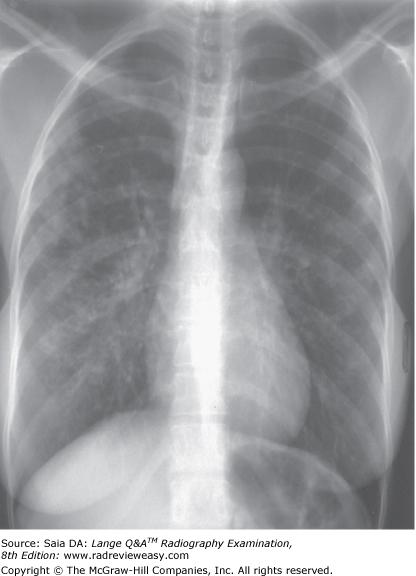

The PA chest image shown in Figure 4–13 exhibits which of the following qualities?

- Adequate penetration of the heart

- Long-scale contrast

- Adequate inspiration

1, 2, and 3